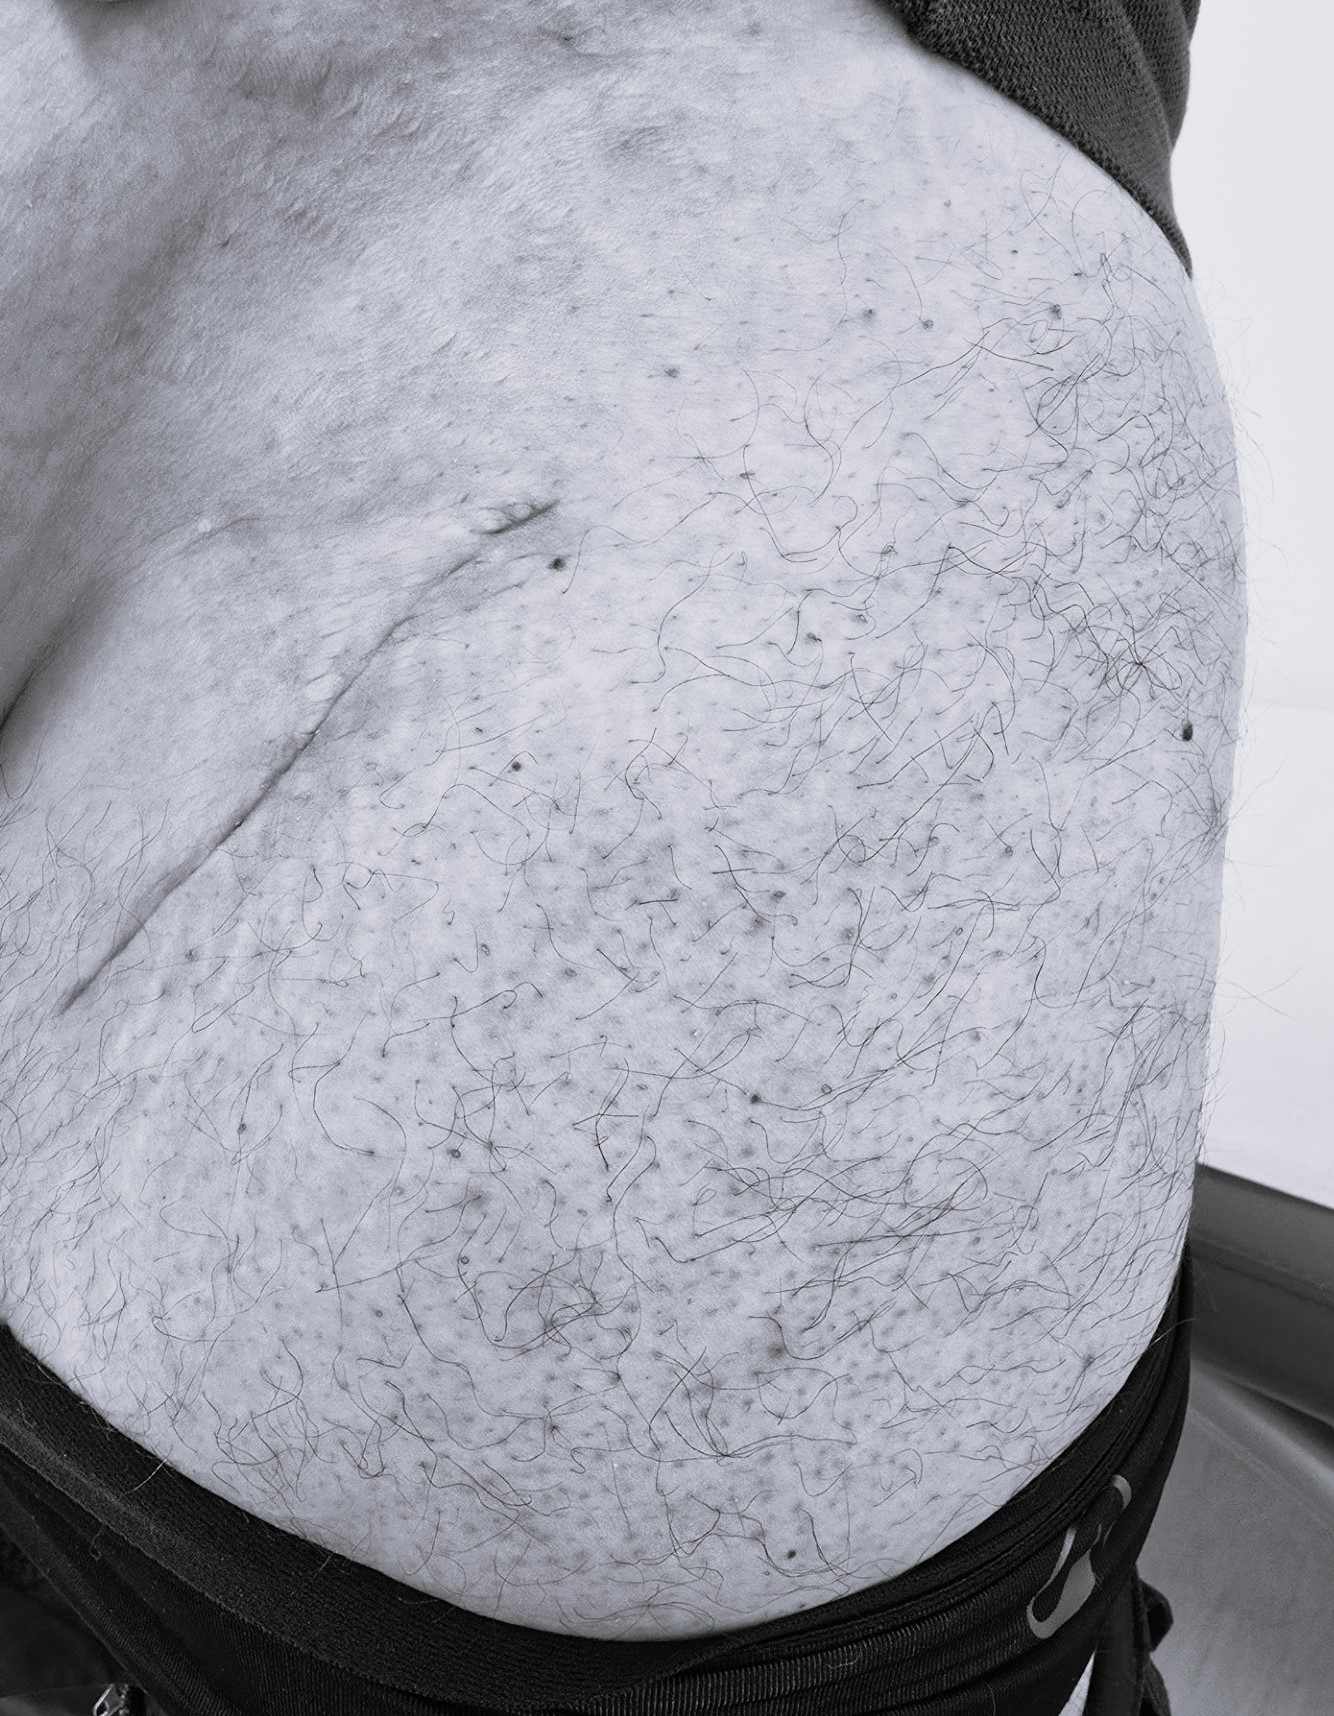

Подготовка на кожата

Никакви инфекции или възпаления на кожата не се допускат преди хирургичната интервенция.

- Естетичен, слабо забележим и с естествен ход оперативен белег

„Бикини“ достъпът следва естествените кожни бразди в зоната на ингвиналната (слабинната) гънка. Следвайки описаните линии на „цепливост“ на кожата, регистрираме повишени оздравителни и регенеративни процеси на оперативната рана, намаляване на ръбцовата тъкан и естетично оформяне на минимален кожен белег.

Проучвания със запитване на пациенти, претърпели смяна на тазобедрената става, показват, че белегът при използван „Бикини“ достъп се възприема като по-естетичен и с по-добра текстура спрямо белезите, получени при други стандартни оперативни достъпи.